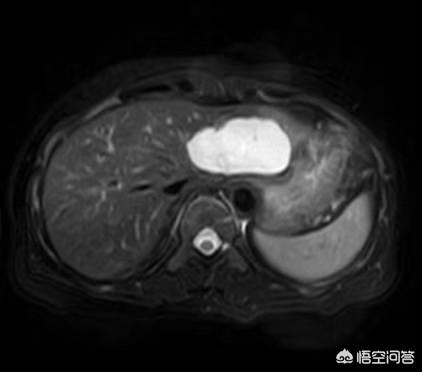

ほとんどの海綿状血管腫は、健康診断の超音波検査で偶然発見される。典型的な病変は超音波、CT、MRでより特徴的な画像を示し、定性的診断は難しくない。超音波検査およびCTの強調像では、典型的に'early out and late in'であり、MRスキャンのT2では'電球徴候'(下図)を示す。